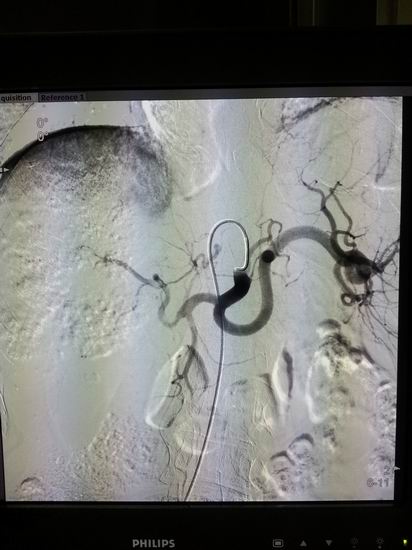

名称:高档数字减影、血管造影系统 Allura Xper FD20

主要功能:采用大平板科技,结合2K影像链,提供极佳图像细节解析能力,1250mA成像能力与“透心凉”高散热球管,“Refresh light”技术消除动态采集时的鬼影,图像质量更高。